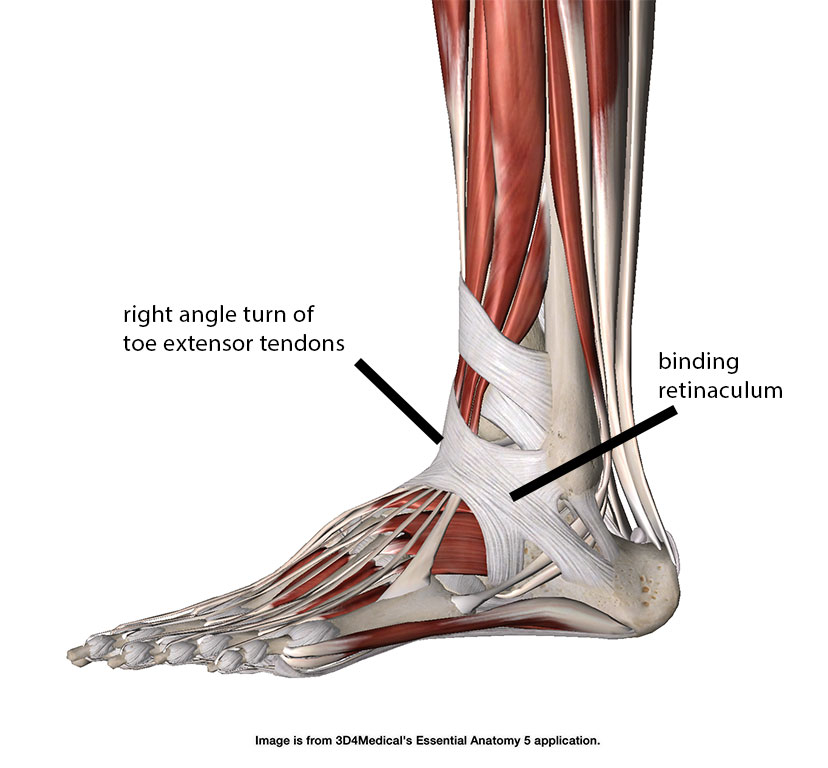

Анатомия голеностопа: Сухожилия и их строение